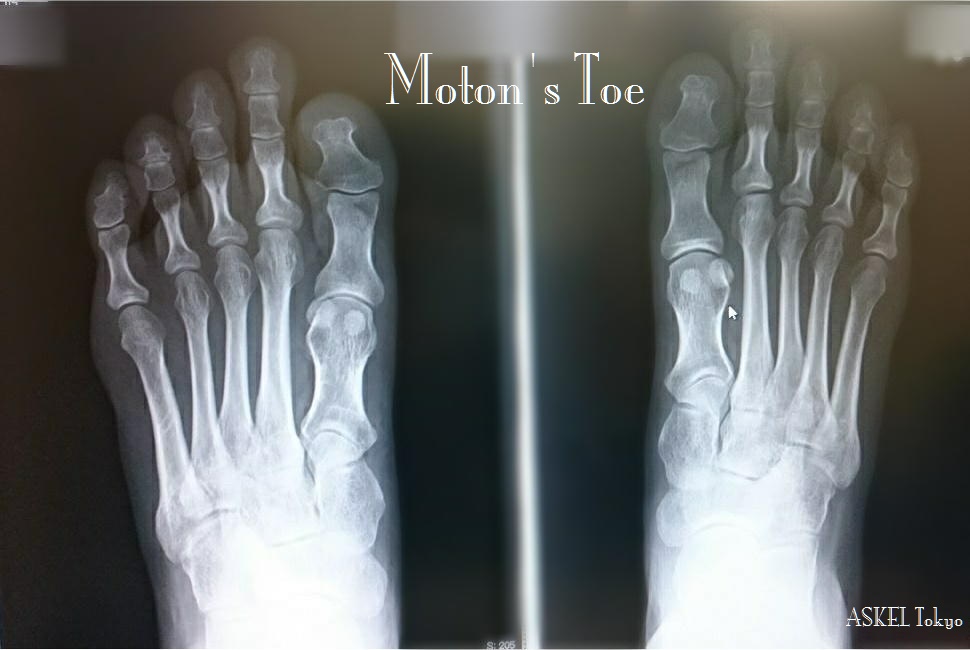

先日、踵周辺と土踏まずの辺りが痛くて診てもらった患者に、整形外科の医師がこの説明をし、その原因と言われるモートン足の動きを指摘し、病気ではないので治療はないが足をよく知ってバ

ランスを整える技術があるところで改善するとよいですとアドバイスを受け、レントゲンを持って来店された

受け取った写真を見るとまさにご指摘の通りで母趾に上手く体重が乗ってこない動きをしている

特に、このタイプの足の方は母趾が繋がる中足骨の動きが多く、過剰運動性と呼ばれる状態になることで様々な筋肉の痛みを引き起こす

第一中足骨と第二中足骨の間の痛み、くるぶし下側の痛み、土踏まず周辺の痛み、踵の痛みなどが代表的な痛みと言われている

踵の痛みは、モートン足の動きが足の前方に及ぼす動きの影響は異常な過回内になる動きを強め、この動きが足の様々な部位に異常なストレスを掛けるようになる

これらによって踵周辺に痛みを生み出す